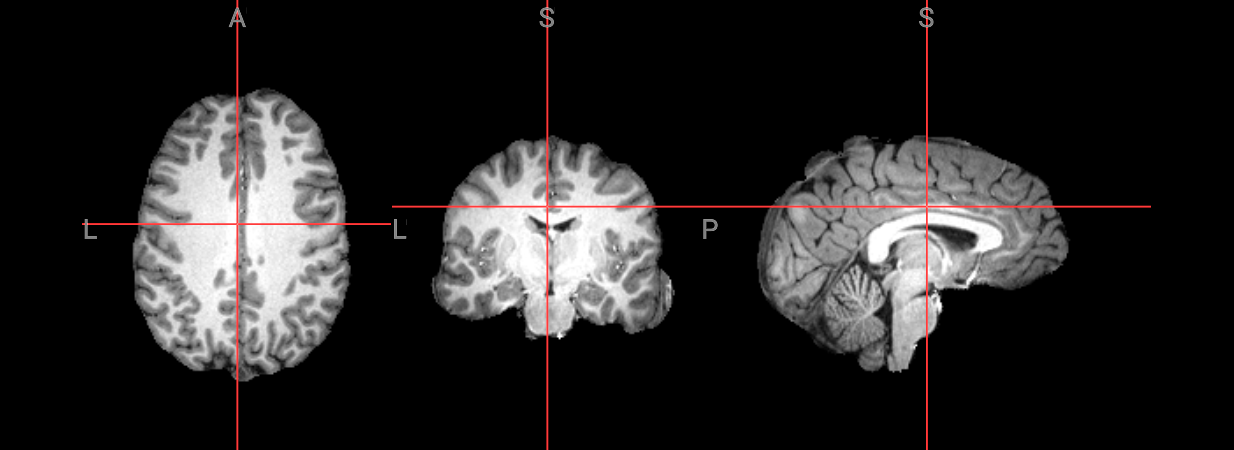

Since fMRI studies focus on brain tissue, our first step is to remove the skull and non-brain areas from the image.

In order to analyze fMRI data, you will need to load an fMRI analysis package. In this example we will use the following packages and algorithms to skull-strip the anatomical image:

Advanced Normalization Tools (ANTs): antsBrainExtraction.sh

Analysis of Functional NeuroImages (AFNI): 3dSkullStrip

FreeSurfer: SynthStrip

FSL (FMRIB Software Library, created by the University of Oxford): BET - Brain Extraction Tool